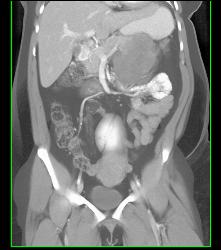

GIST Tumor